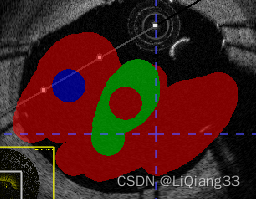

paint over续:使用Active Label=Label1; paint Over=Clear Label标注时,只允许对没有标注的区域标注,如图,同样的,如果paint over=Label1(red), active label = label3则蓝色只能在红色上标注

- 使用画笔工具进行涂画,选择不同的大小进行边界以及内容的填充,选择边界自适应填充可以根据不同的CT值,来填充不同的区域

- 最终的效果